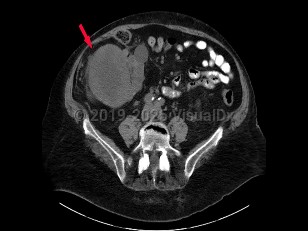

Clinical presentation includes hematuria, abdominal pain, flank mass or abdominal mass, fever, weight loss, anemia, or varicocele. Many patients have tumors discovered incidentally with abdominal imaging performed for another reason.